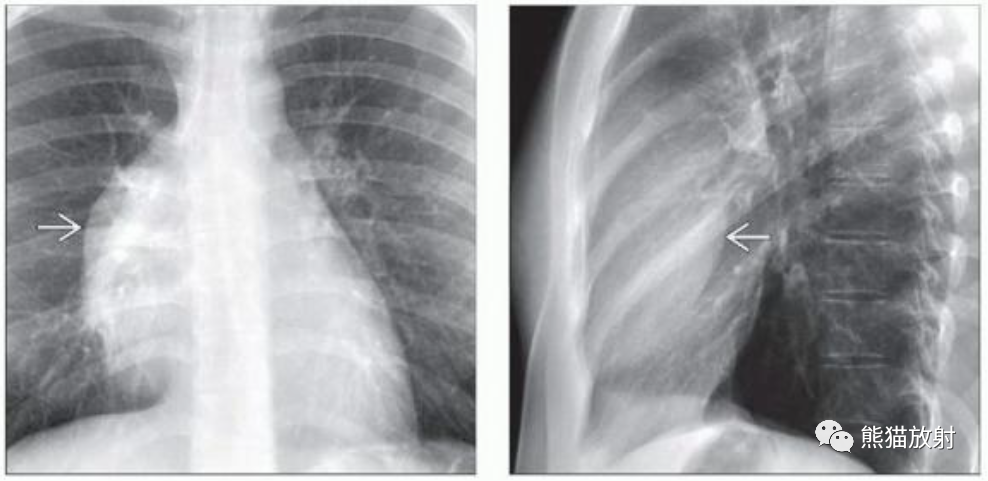

(左)25岁男性,成熟性囊性畸胎瘤。PA胸片显示右前纵隔肿块,边缘平滑,可见肺门重叠征,透过病变可见右侧肺动脉。

(右)同一患者的侧位胸片显示肿块投影于心脏前部,证实了病变位于前纵隔。成熟畸胎瘤患者通常是1至40岁的年轻男性或女性。